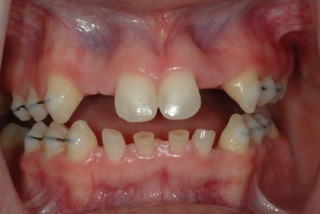

The final treatment plan was outlined for Jessica and her parents. Resin-bonded bridges would be utilized as the interim restoration of choice to provide esthetics and function until the implant phase could be initiated. The additive tooth dimension changes would be duplicated from the wax-up, using silicone templates as guides. The silicone indices would act as preparation guides for primary tooth reduction before the bonded bridges are placed.

The resin-bonded bridges were pre-made from duplicate wax-up models. Ribbond was incorporated into the lingual wings of the upper and lower anterior bridges. Glass-span ropes were utilized for structural support in the posterior bridges.

The upper posterior resin bridges were adhered to the abutment teeth. Jessica elected not to have the lower bridge fabricated to save expense. Following composite additions to the maxillary cuspids, the lateral incisor resin bridges were secured with flowable composite.

Once the lower anterior primary teeth were prepared, the lower bridge was tried in and adjusted for esthetics and function. It was luted with flowable composite to the remaining enamel.